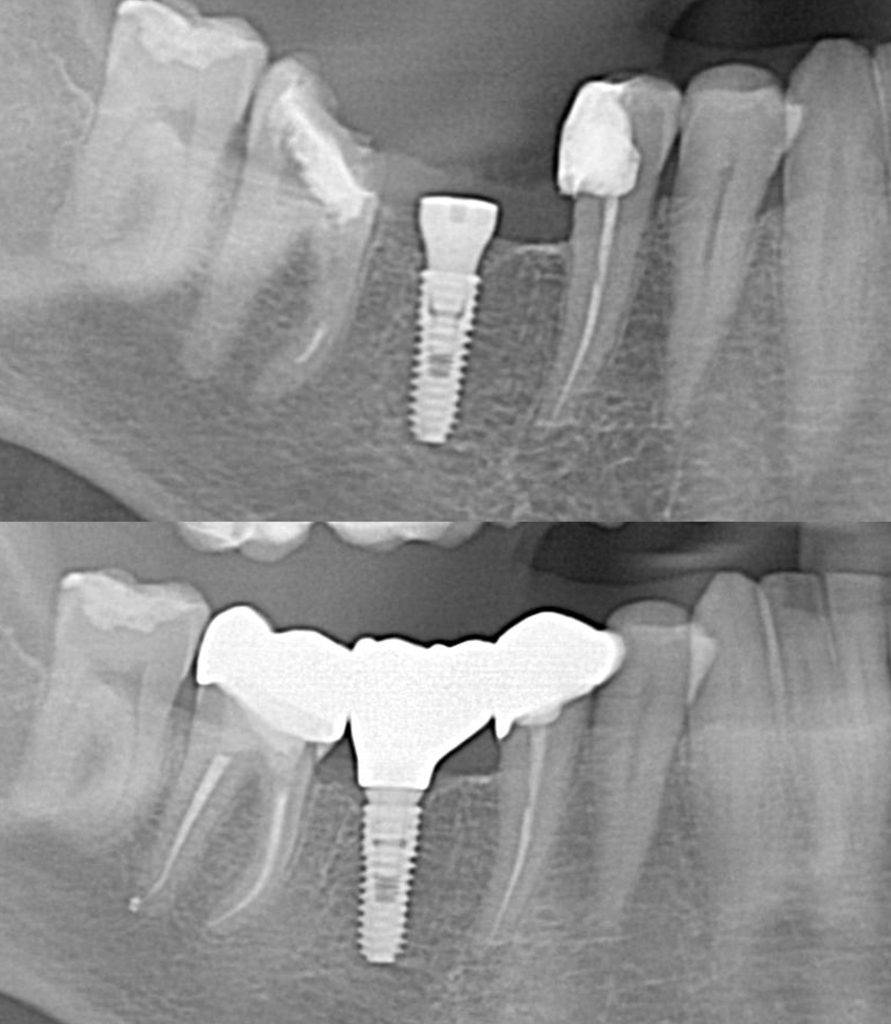

Dental implant surgery is a procedure that replaces tooth roots with metal, screwlike posts and replaces damaged or missing teeth with artificial teeth that look and function much like real ones. Dental implant surgery can offer a welcome alternative to dentures or bridgework that doesn’t fit well and can offer an option when a lack […]